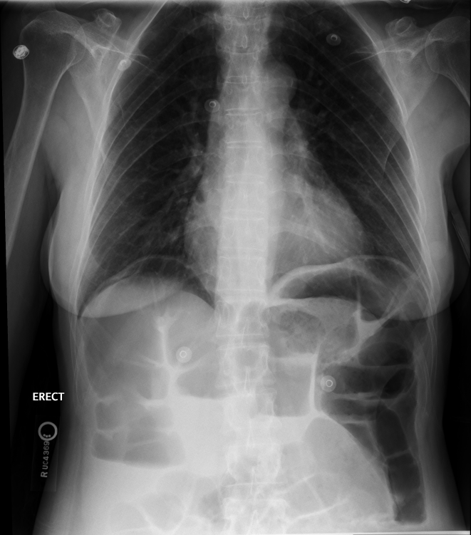

patient w/ pneumoperitoneum

what is this an image of?

pneumoperitoneum

free air in the peritoneal cavity

usually from a perforation

recent abdominal surgery & perforation of hollow abdominal vsicera

trauma to abdominal wall w/ penetrating injury

what are the causes of pneumoperitoneum?

subtractive → decrease technique due to additional air

what are the tehcniques for a patient w/ pneumoperitoneum?